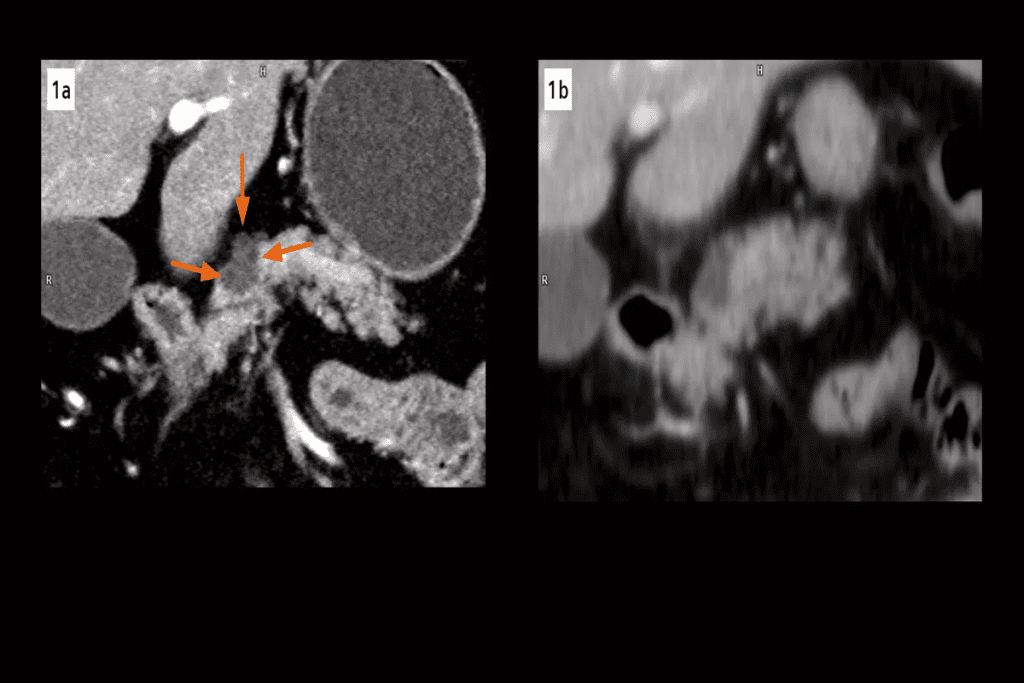

Imaging studies are vital for lung nodule checks. Computed Tomography (CT) scans give detailed lung images. They help track nodule size and shape over time.

Positron Emission Tomography (PET) scans show how active the nodule is. This can tell if it’s cancer. Magnetic Resonance Imaging (MRI) is less used but helpful in some cases.